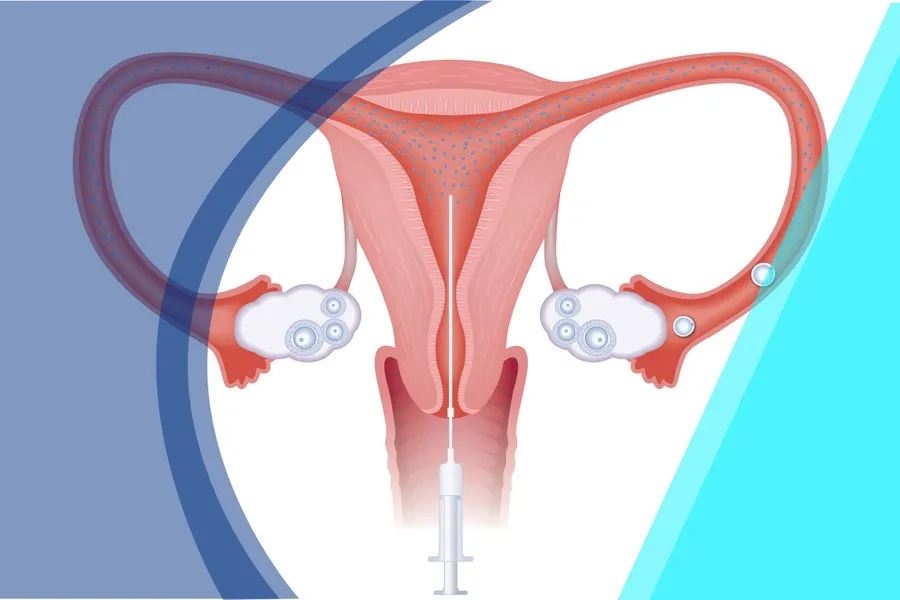

Tuy nhiên, điều kiện then chốt để thực hiện IUI là buồng trứng và ít nhất một ống dẫn trứng phải thông suốt, đảm bảo tinh trùng có thể gặp trứng. Đồng thời, tinh dịch của người chồng cần ở mức bình thường hoặc chỉ có các bất thường nhẹ đến vừa, đủ để tiến hành chọn lọc tinh trùng chất lượng cao cho quá trình bơm.

Điều kiện để thực hiện IUI là buồng trứng và ít nhất 1 ống dẫn trứng phải thông suốt để tạo cơ hội tinh trùng gặp trứng

3. Chất lượng nang noãn và tình trạng tử cung

Hiệu quả IUI phụ thuộc nhiều vào tình trạng tử cung và chất lượng nang trứng. Nội mạc tử cung cần đủ tốt và từ 1-2 nang trứng đạt tiêu chuẩn về kích thước vào ngày kích thích rụng trứng. Với phụ nữ mắc lạc nội mạc tử cung nặng, tổn thương ống dẫn trứng hoặc tinh trùng bất thường nặng có thể làm giảm hiệu quả của IUI, khi đó IVF thường là lựa chọn ưu tiên.

Chất lượng nang noãn là yếu tố quan trọng hỗ trợ tăng cơ hội thụ thai